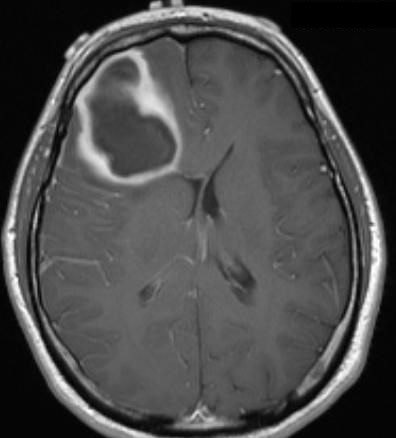

MRI brain showing ring-enhancing lesion in the right frontal lobe with surrounding oedema